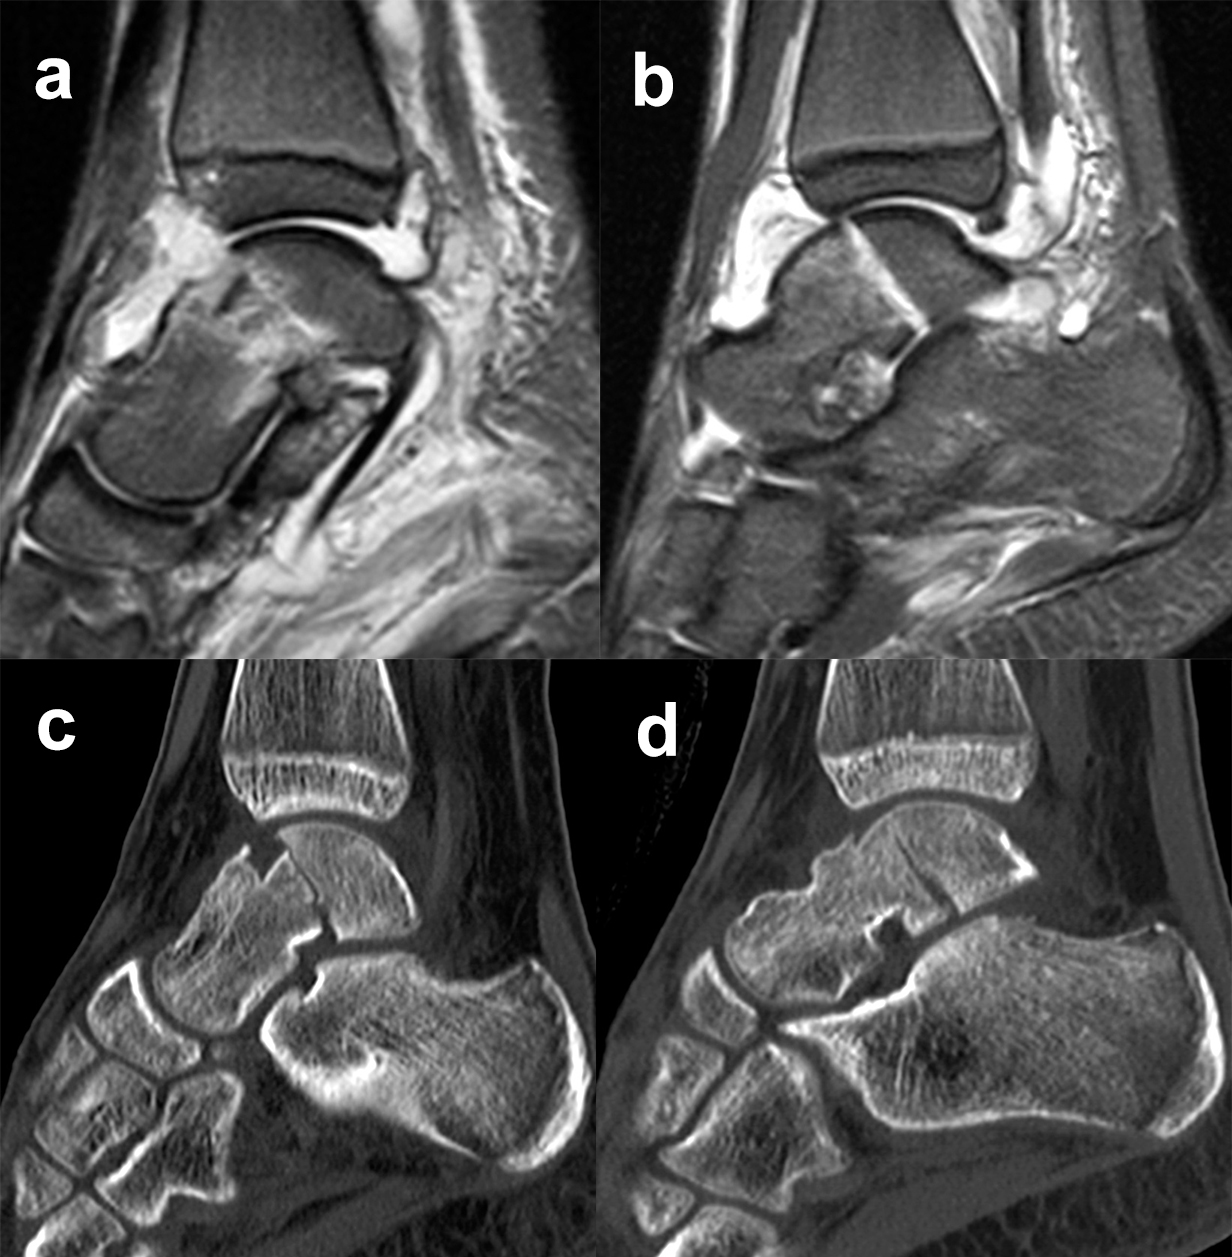

Bei in den konventionellen Aufnahmen nicht sicher auszuschließender Talusfraktur bzw. zur genauen Darstellung der Dislokation bei Taluskorpus- oder Talushalsfraktur sollte die Indikation zur CT-Diagnostik großzügig gestellt werden (Abb. 1 c, d). Insbesondere dient die CT-Diagnostik zur genauen Evaluierung der Frakturmorphologie und OP-Planung sowie auch zur Vermeidung möglicher übersehener peripherer Talusfrakturen 4.

Eine MRT-Untersuchung ist zur Primärdiagnostik nicht erforderlich, kann jedoch im Einzelfall Knorpel-, Band- und Sehnenverletzungen erkennen lassen. Eine Ausnahme stellt die Diagnose von Stressfrakturen des Talus dar, hierfür ist die MRT das Diagnostikum der Wahl 15. Für die Früherkennung einer avaskulären Nekrose oder Beurteilung der Revaskularisierung nach Fraktur ist die MRT von eingeschränkter Relevanz, da die Befunde vom Frakturödem überlagert werden 16.

Die Zugänge zu dislozierten Taluskorpusfrakturen entsprechen im Wesentlichen denen bei Talushalsfraktur. Bei weit in den zentralen und hinteren Taluskorpus hineinreichenden Frakturen kann zur ausreichenden Übersicht und verbesserten Fragmentmanipulation eine Innenknöchelosteotomie erforderlich werden, sofern der Innenknöchel nicht ohnehin mit frakturiert ist 4. Hierzu wird der anteromediale Zugang nach proximal erweitert. Die Schraubenkanäle werden vorgeborht um eine exakte Refixierung des Innenknöchels nach der Talusosteosynthese zu gewährleisten. Die Osteotomie wird schräg auf den medialen Gelenkwinkel geführt, im eigenen Vorgehen zur besseren Stabilisierung vorzugsweise als Chevron-Osteotomie. Das Subtalargelenk ist bei Taluskorpusfrakturen regelhaft frakturiert und disloziert (Abb. 11). Zur Reposition und Überprüfung der Gelenkkongruenz im Subtalargelenk wird ein zusätzlicher anterolateraler Zugang benötigt.

Die anatomische Reposition erfolgt schrittweise unter direkter visueller Kontrolle von medial und lateral. Die temporäre Retention wird wiederum mit Kirschnerdrähten erzielt (Abb. 12). Die Hauptfragmente werden durch Schrauben, die unter Knorpelniveau versenkt werden, fixiert. Bei sagittalen Taluskorpusfrakturen werden daher vorzugsweise Doppelgewindeschrauben verwendet 34. Zur Fixierung kleinerer osteochondraler Fragmente werden vorzugsweise resorbierbare Stifte verwendet (Abb. 13). Zur Stabilisierung ausgedehnter medialer oder lateraler Trümmerzonen können anatomisch angepasste winkelstabile Platten verwendet werden. Bei diesen ist darauf zu achten, dass diese weder das Talonavicular-Gelenk noch den Innenknöchel irritieren. Gleiches gilt auch für Taluskopffrakturen, welche jedoch eher im Rahmen von Chopart-Luxationsfrakturen entstehen 12.